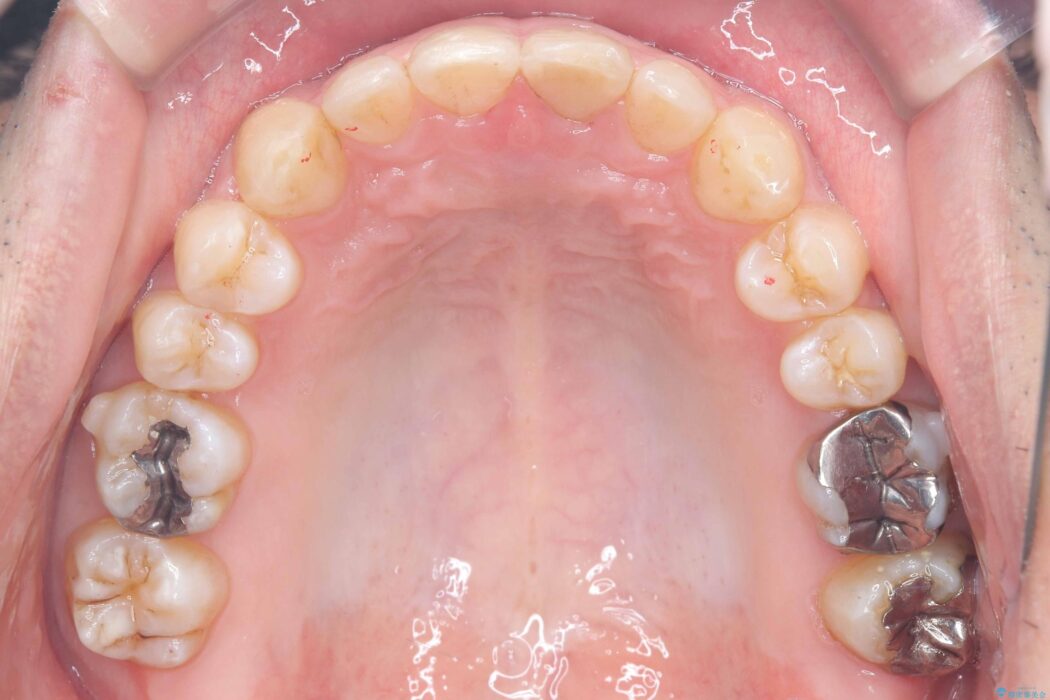

歯の隙間とデコボコ、シザーズバイトも改善され、咬み合わせや見た目が整い、患者様にも大変ご満足いただけました。